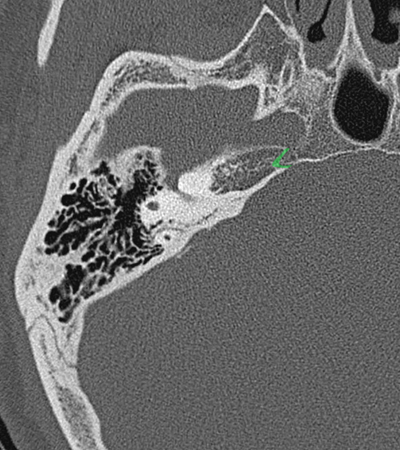

Temporal bone Petrous apex Sphenoido-temporal suture Occipitotemporal suture Petroclival suture

Radioanatomy of Temporal bone